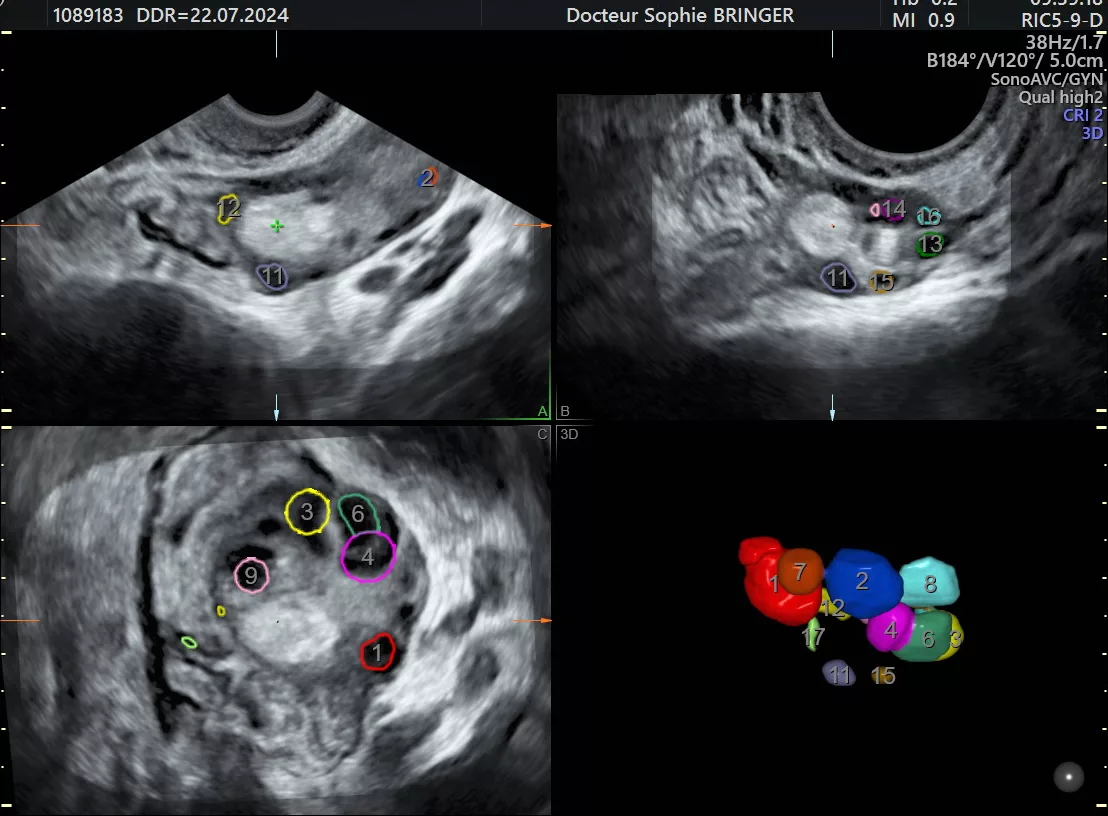

- Échographie en début de cycle (3ème – 5ème jour du cycle). Recherche des causes d’infertilité : pathologie de la cavité utérine, anomalie des trompes (hydrosalpinx), et évaluation de la réserve ovarienne avec le compte des follicule antraux (CFA).

- Échographies, dites de monitorage de l’ovulation. Étudie le nombre et la croissance des follicules ovariens et de l’épaisseur de l’endomètre dans le cadre d’un traitement de stimulation ovarienne.